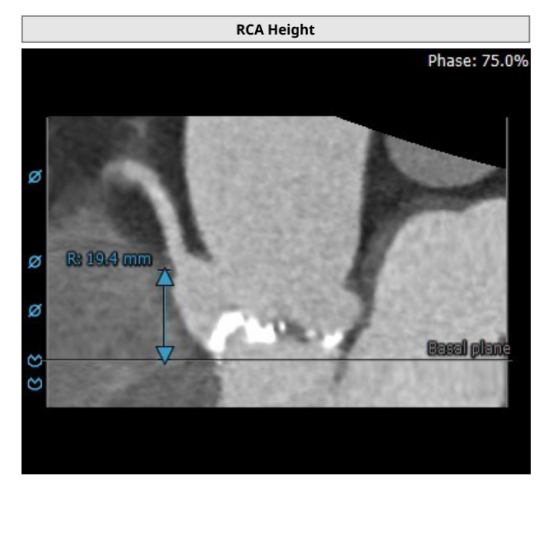

左冠高度:13.0mm,右冠高度:19.4mm

左冠高度:20.1mm,右冠高度:19.5mm